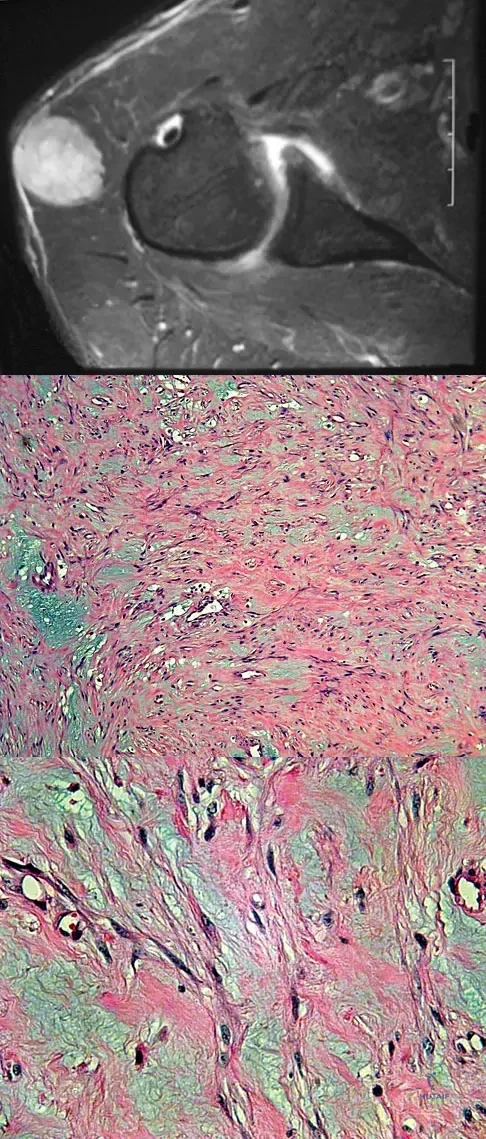

Question 39

A 35-year-old patient has right hip pain. Figures 34a and 34b show the coronal MRI scan and the biopsy specimen. What is the most likely diagnosis?

Explanation